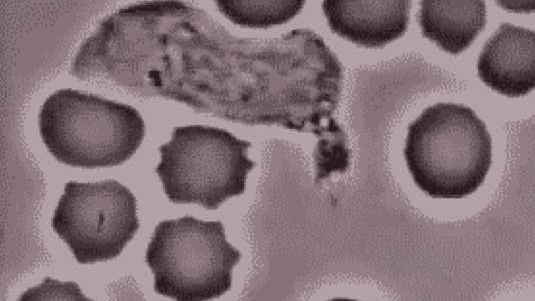

Quiz Biology Quiz z biologii. Czy znasz wszystkie odpowiedzi?